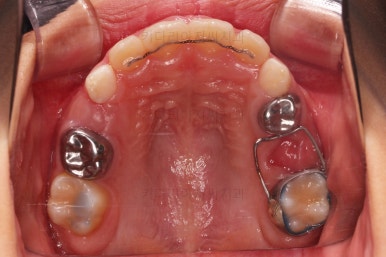

치료가 도저히 불가능한 유치는 발치를 하고, 대신 영구치가 나오기까지 매우 오래 걸릴 것으로 예상되어서 주위 치아들의 위치가 잘 유지되라고 공간유지장치를 해줬어요.

전문 용어로 band&loop라고 하는 이렇게 해줘야 추후에 또 다른 더 큰 문제가 생기지 않는답니다.

제 시기보다 한참이나 먼저 빠진 유치는 치아 공간유지장치를 꼭 염두에 두세요.